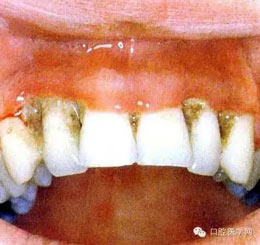

(三)齦炎: 齦緣呈一條火紅色帶或口腔無其他異常而牙齦呈局灶性腫。

(四)壞死性齦炎:為局限的或普遍的潰瘍形成,牙間乳頭破壞,并伴有纖維蛋白性壞死。

(五)牙周炎:為牙周軟組織喪失及不規(guī)則骨破壞,可有明顯的疼痛。(早期)牙周炎軟組織損害呈火山口樣。